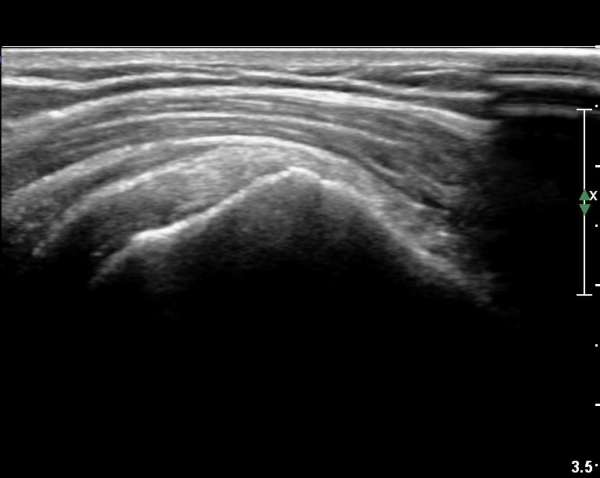

¿À±¸µ¹±â°ßºÀÀδë Á¾´Ü¸é°Ë»ç¿¡¼­ ƯÀÌ ¼Ò°ßÀ» º¸ÀÌÁö ¾ÊÀ¸³ª(»çÁø 1)

ŽÃËÀÚ¸¦ ¾à°£ °ßºÀ ¸»´ÜÀ¸·Î ³»¸®³ª ¿À±¸µ¹±â°ßºÀÀδëÀÇ ¼®È¸È­°¡ °üÂûµÈ´Ù(»çÁø 2).